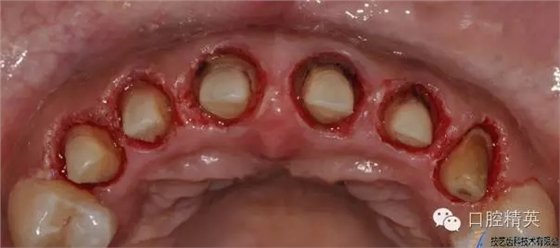

水激光切除牙齦

640.webp (12).jpg